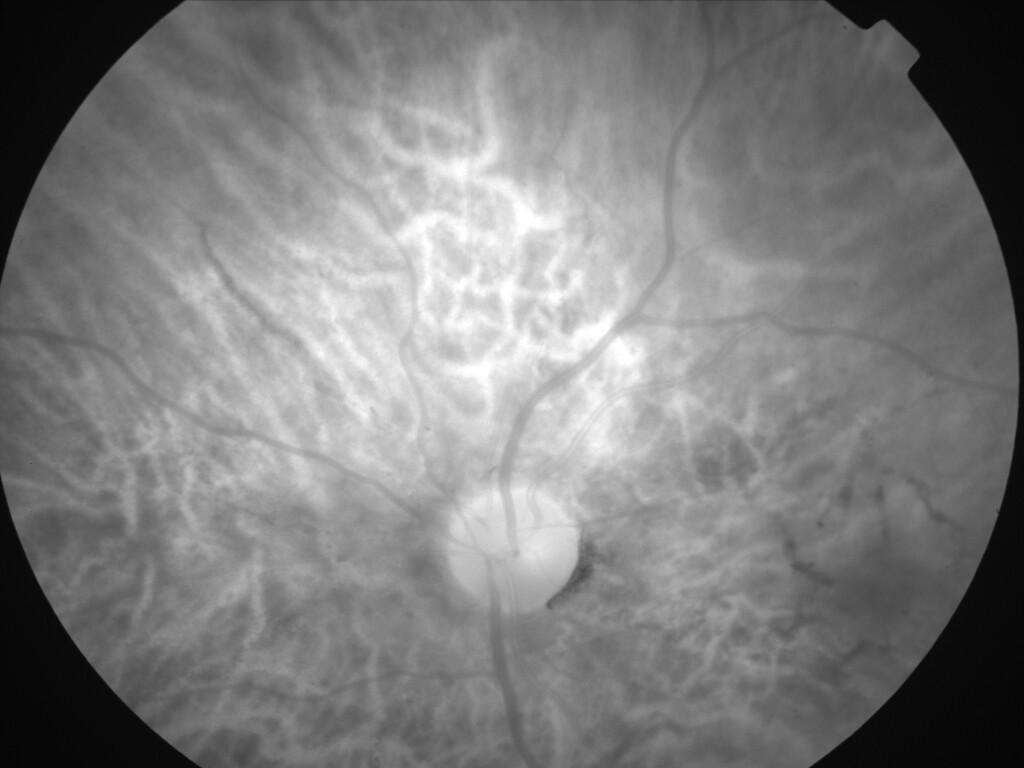

ASSOCIATION STRIES ANGIOIDES ET DYSROPHIE MACULAIRE RETICULEE

NEOVASCULARISATION